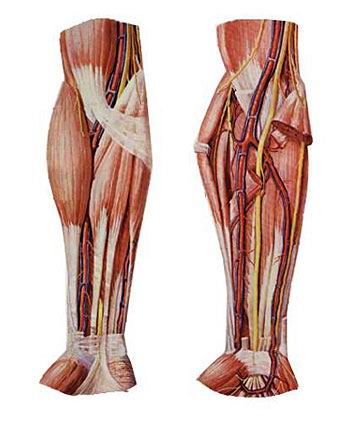

1)胫神经 1) tibial nerve

沿腘窝中线,经小腿后群肌深浅两层间下降,于内踝后方至足底分为足底内侧神经和足底外侧神经。 Popliteal fossa along the midline, after the calf muscle depth between the two groups decreased in the medial malleolus to the rear foot into the medial plantar nerve and lateral plantar nerves.

胫神经肌支支配小腿后群肌、足底肌。 Tibial nerve calf muscle branches after dominating muscle group, plantar muscles. 皮支布于膝关节、小腿后面皮肤、足底皮肤。 Cutaneous branches distributed in the knee, back calf skin, foot skin. 胫神经损伤后表现为足“勾状外翻”。 Posterior tibial nerve injury manifested as foot "hook-shaped valgus."

2)腓总神经 2) peroneal nerve

沿腘窝上外侧缘向外,绕腓骨胫,分为腓浅、腓深神经。 Popliteal fossa along the outer edge of the outward around the tibia fibula, into superficial peroneal, deep peroneal nerve. 腓浅神经肌支支配小腿外侧群肌,腓深神经肌支支配小腿前群肌。 Superficial peroneal nerve muscular branches dominated lateral leg muscle groups, deep peroneal nerve muscular branches dominated front leg muscle groups. 腓总神经损伤后表现为足下垂伴内翻(即“马蹄内翻”)。 Peroneal nerve injury manifested as foot drop with varus (ie "clubfoot").